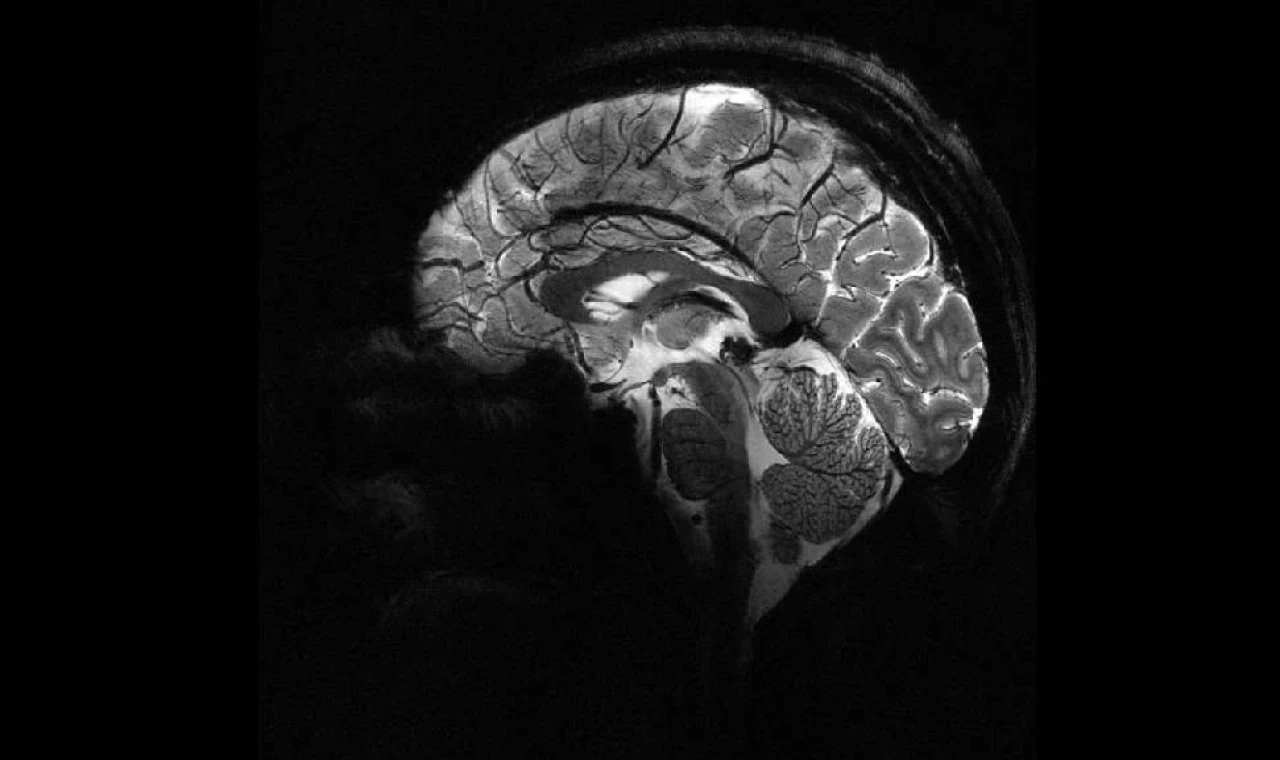

Beynin hafıza merkezinin yeni bir özelliği keşfedildi

Beynin hafızadan sorumlu bölümü hipokampusun, anıları yeniden düzenleyerek gelecekteki sonuçları öngördüğü bulundu.

Hipokampus, fiziksel alan ve geçmiş deneyimlerin haritalarını oluşturarak kişinin, etrafındaki dünyayı anlamasını sağlıyor.